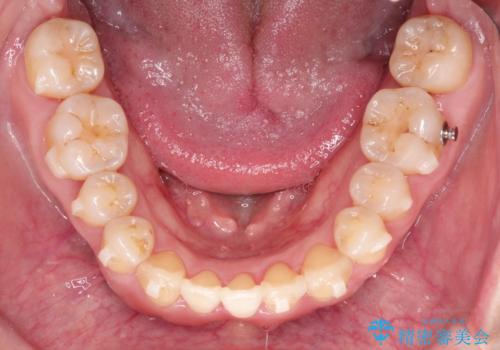

- 前歯の噛み合わせが悪いことを主訴に来院されました。

歯周病も併発していたため、歯牙への負担が少なくなるように治療計画をたて、インビザラインにて治療を完了しました。

矯正開始前に半年間、歯周治療を行ってからインビザラインを装着しています。